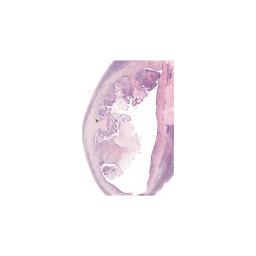

0_0.jpeg 2019-11-14 12:32 4.1K